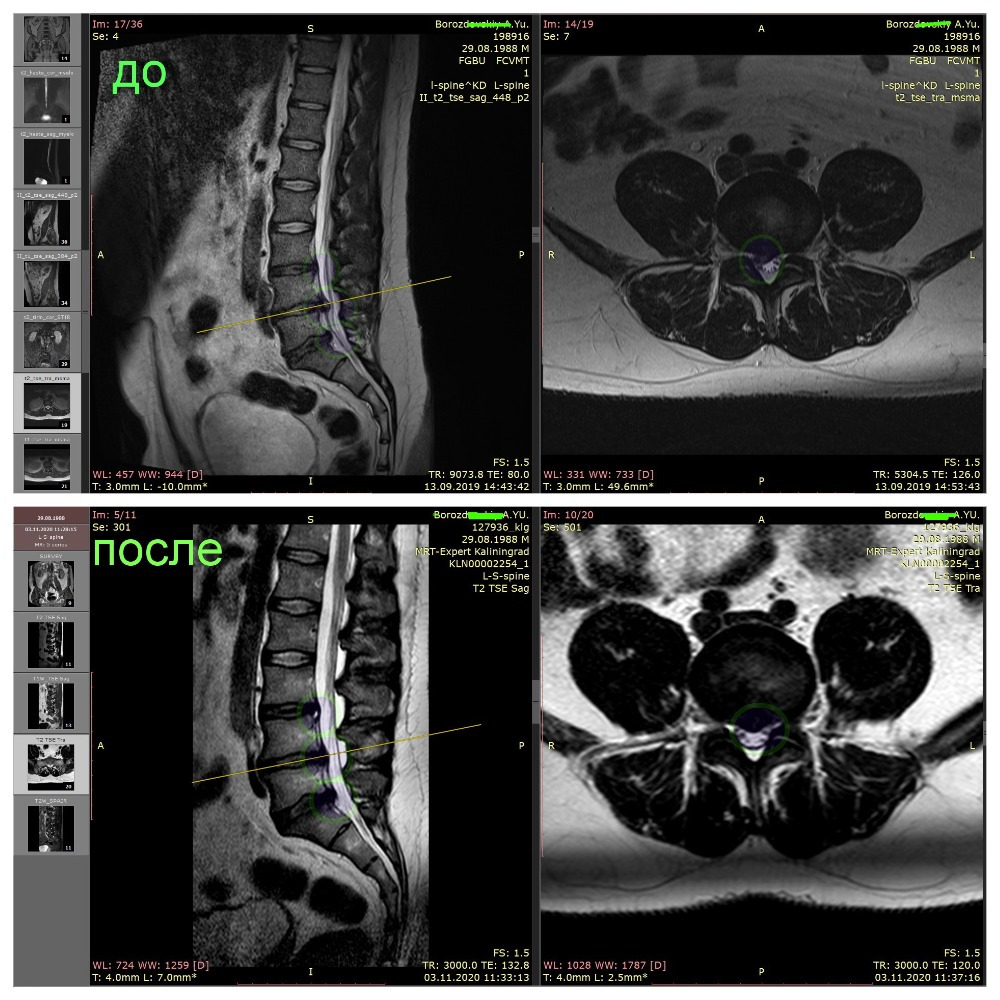

Примеры лизирования грыж

и секвестров

(Резорбция межпозвонковой грыжи)

выполненные главным врачем клиники Халанским Н.Н.